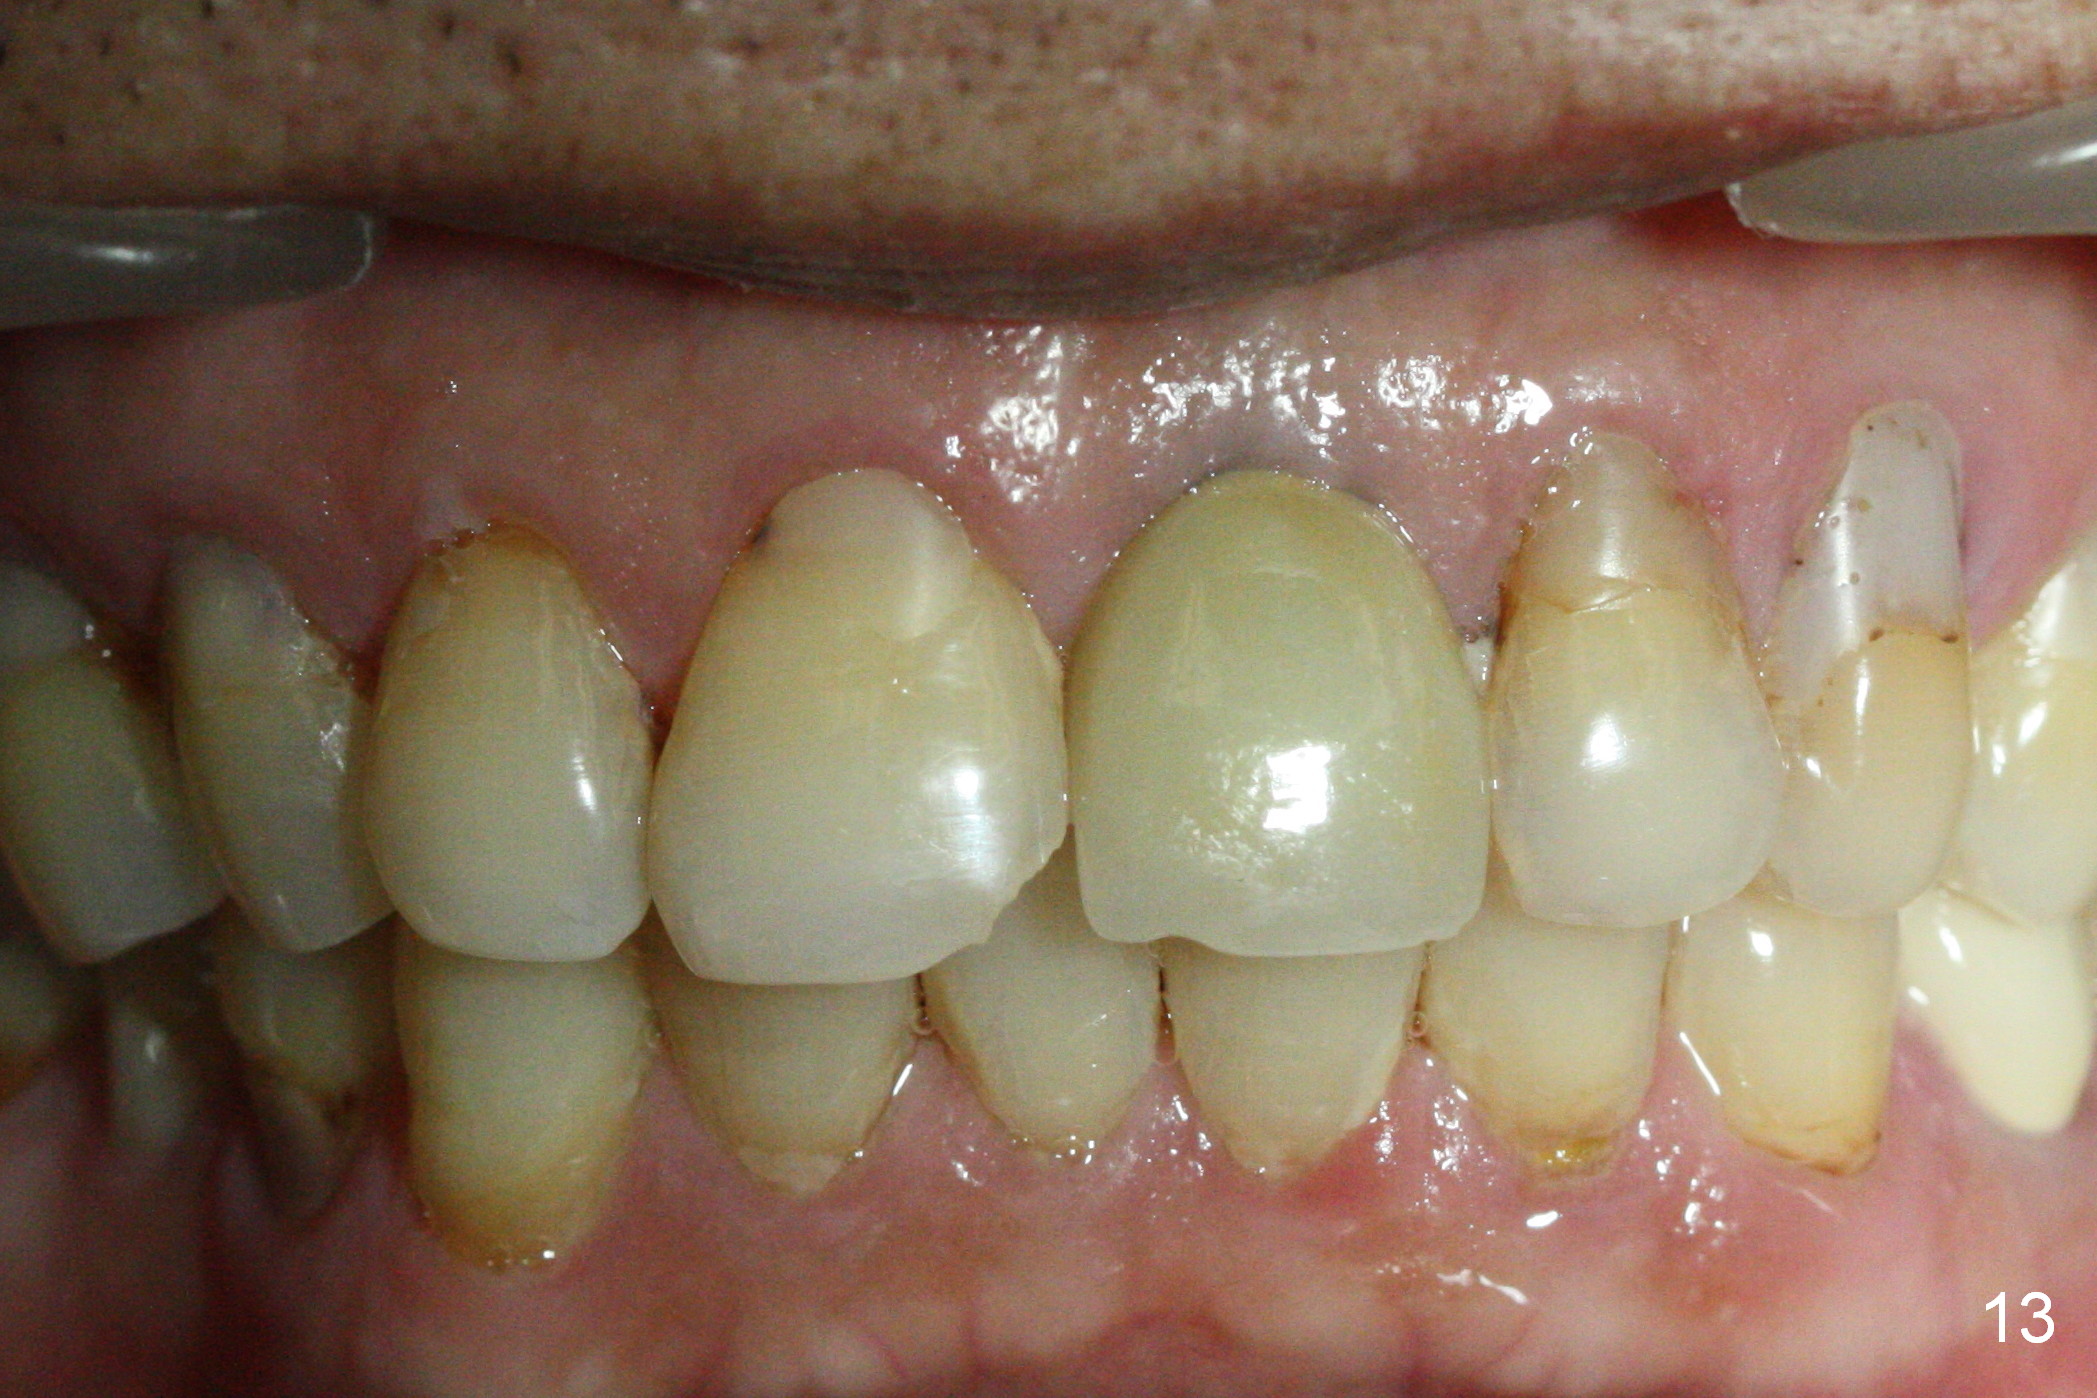

Postop tenderness lasts for two days. The palatal swelling is unnoticeable 7 days postop (Fig.9 *, as compared to A in Fig.8). The bone remains stable around the implant (Fig.10), while the gingiva healthy around the immediate provisional (Fig.11) 5 months postop. Due to insurance limit, the permanent restoration is delayed (16 months postop, Fig.12). The patient is satisfied with the function and appearance 3 years 8 months postop (21 months post cementation, Fig.13,14). PA is taken 4 years 1 month postop (2.5 years post cementation, Fig.15). The lamina dura forms from the most coronal threads (Fig.16). Although there is no bone loss around the implant (Fig.17), metal starts to show 5 years 2 months postop (Fig.18 ^), probably related to the buccal placement, too large the implant for the site or buccal plate atrophy (Fig.19).